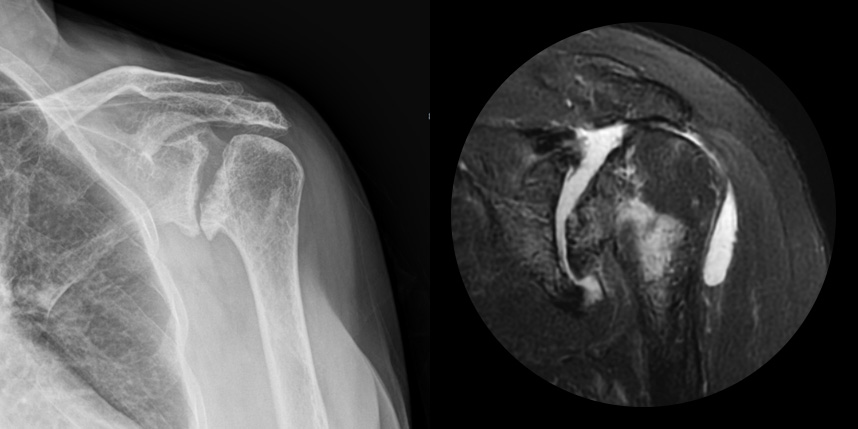

발생부위와 원인으로는 퇴생성, 골절이나 탈구 등 외상의 합병증, 류마티스, 진행된 회전근개파열, 골괴사 등에 의해 발생하게 됩니다.

주로 젊은 층에서는 외상, 류마티스 관절염, 수술 등에 의해 2차적으로, 50대 이후에는 퇴행성으로 생기게 됩니다.

어깨 퇴행성은 많이 써서 닳고 노화에 따른 변화가 생긴 것으로, 말 그대로 어깨가 많이 사용되면서 연골이 닳아서

마모돼어 생기는 관절염입니다. 어깨 회전근개 관절병증 원인으로는 어깨 힘줄 파열을 방치했을 때 관절이 틀어진 상태에서 계속

사용하게 되면 관절이 많이 상해서 관절염까지 진행되며, 이런 경우 회전근개파열의 결과로 생긴 관절병이라고 합니다.

비수술 치료에도 호전이 없는 경도의 관절염에서 시행합니다.